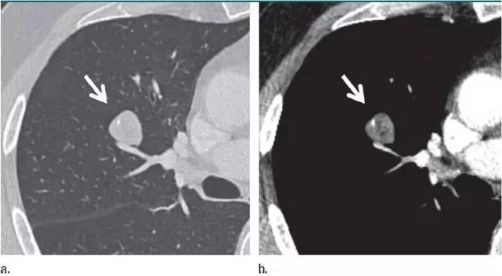

双肺粟粒样转移和肝脏转移明显缩小